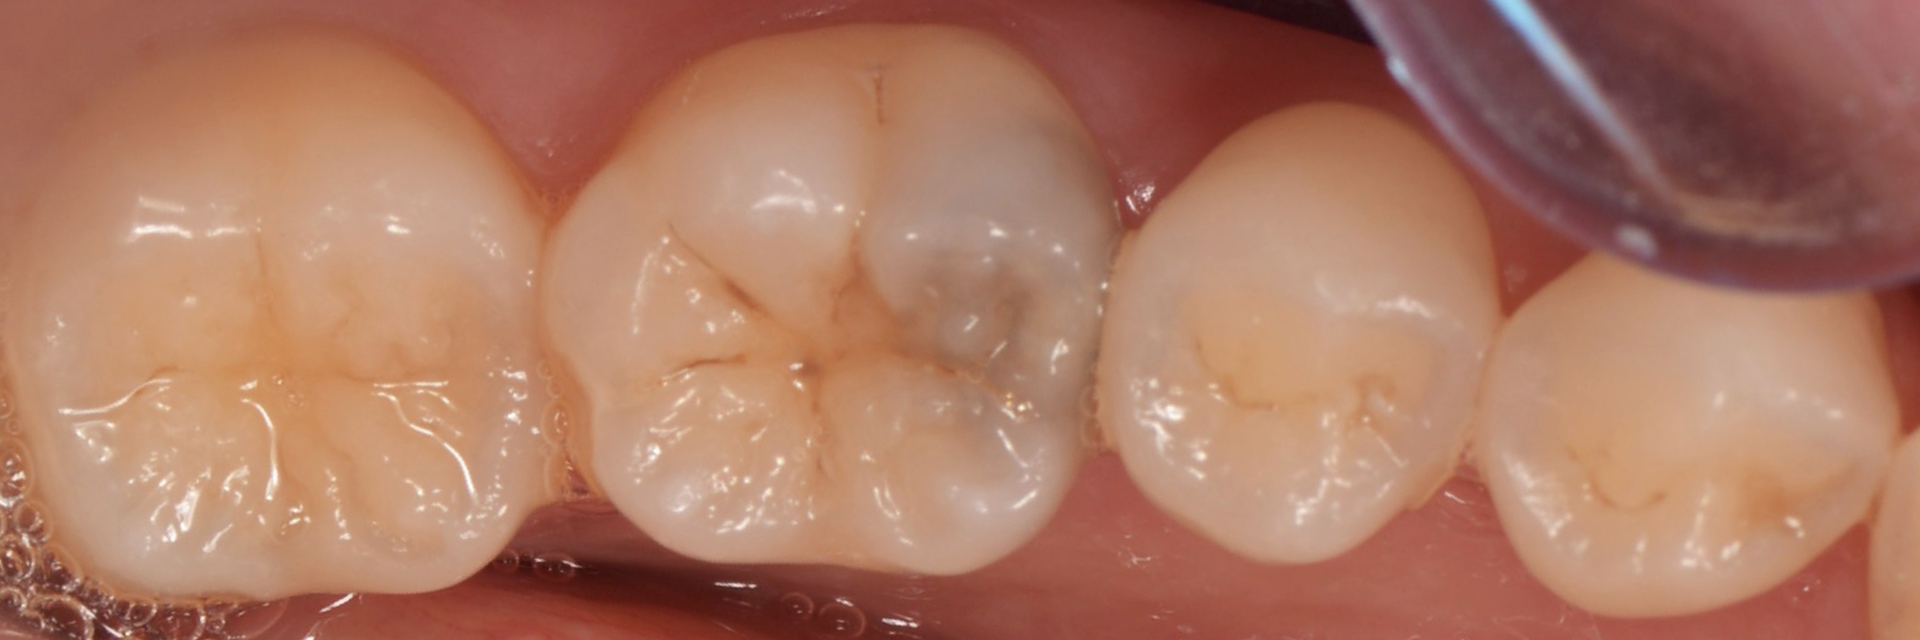

- 治療前

| 治療内容 | 今まで一度も治療の既往がない場合、治療方法の第一選択はダイレクトボンディングです。 型取りが必要ないので最低限の切削量で処置が可能です。 |